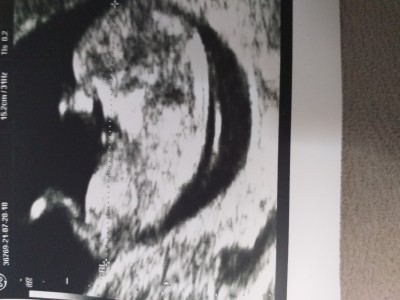

Cinsiyet tahmini yapabilen var mi

Kaç haftalıksın canım

11+5 haftaligim

Kız gibi Allah gönlüne gore versin

Rabbim gönlünden geçeni nasip etsin inşallah canım ama bnde kıza benzettim sanki yinede rabbim bilir hayırlı sağlıklı olsunlar da gerisi önemli değil gülüm❤️❤️❤️❤️❤️

Aynen oyle bir oglum var bir de kizim olsun cok isterim ama onceligi elbetteki sagligi dr umuz belirsiz konustu cikinti var erkek olabilir ama belli degil tam olarak beklicez dedi o yuzden merak ettim :)

Aşkım erkek bebekler daha belirgin oluyor gülüm bnim tam 12 haftalıkken kesin erkek dedi pipisinide gösterdi bu dağınık gibi o yüzden kız dedim içimden de kız geçti ne yalan soylim canim ❤️